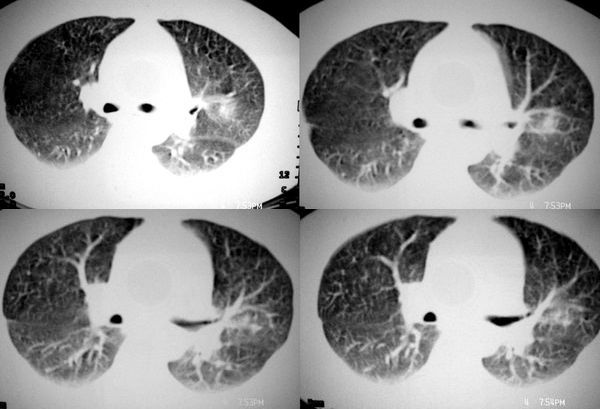

③球型肺炎:中央密度高边缘较淡,呈晕样改变;广泛胸膜增厚;病灶呈方形,周围可见斑状、薄片影,周围血管纹理多、增粗,无僵直和牵拉;临床上有起病急变化快,抗炎治疗效果明显,病程短等特征。